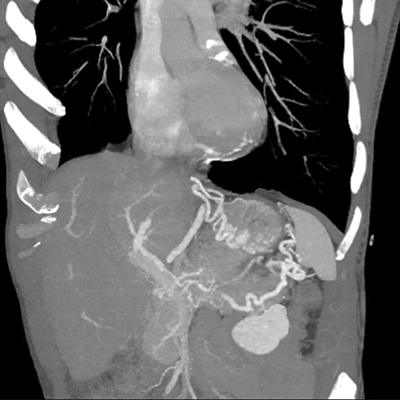

Figure 2

CT performed during portal phase, Maximum Intensity Projection 3D-reconstruction showing splenic vein thrombosis with subsequent gastro-epiploic and fundus varices.